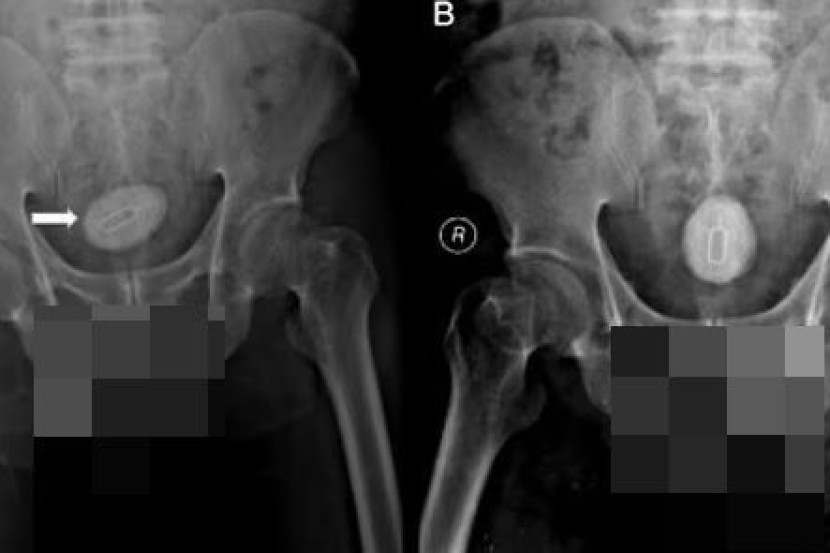

Imbasan x-ray yang dibuat menunjukkan kehadiran objek menyerupai wayar yang tersangkut di dalam zakarnya.

Selain itu, dia juga memasukkan alat yang digunakan untuk memasang kad sim ke dalam zakarnya.